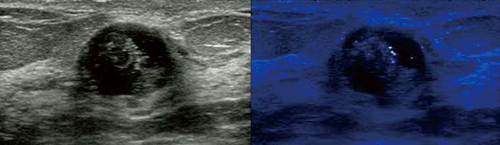

●Precision Imaging(図1)

ノイズ成分を低減し,コントラスト分解能や均一性,組織の連続性を高める東芝独自のイメージング技術です。“Differential-THI”や“ApliPure”などの高画質技術とも組み合わせて使用でき,微細な組織の描出能を損なうことなく,腫瘍などの境界をより明瞭に描出し,その視認性を高めることができます。

図1 従来画像(左)とPrecision Imaging(右)